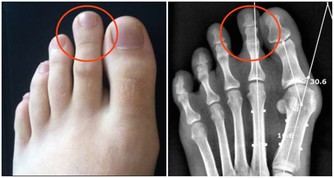

同吃易形成結石

同吃易生結石

影響人體對鈣的吸收,長期食用易導致結石。